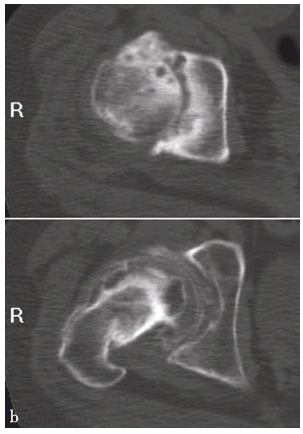

双侧髋臼发育不良伴退行性骨关节病

CT平扫,示双侧髋臼前断面角变小,头臼包容差,髋臼及股骨头轻度骨质增生

髋臼前断面角变小,后断面角小于正常;股骨头顶部层面见不到顶唇,且前后唇变短;股骨头稍向前方移位;伴发关节退行性改变,可见关节间隙变窄,关节面硬化并关节面下囊变,同时髋臼前唇和上部边缘可见骨质增生。有时可合并关节积液。